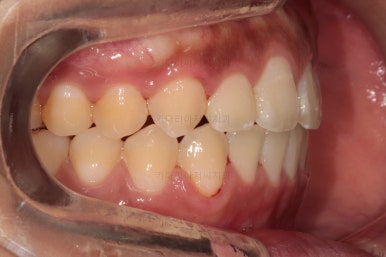

부산치아교정치과 초진 시 입안의 모습입니다.

앞니쪽이 위아래 모두 삐뚠 상태였고요.

왼쪽은 덧니로 툭 튀어나가 있고, 상대적으로 작은 앞니는 안으로 말려 들어가 아랫니와도 거꾸로 물리는 상태였습니다.

어금니도 물론 약간 삐뚤긴 하지만 앞니만큼 심한 상태는 아니었고 맞물리는 기능도 큰 불편함은 없으신 상태였습니다.